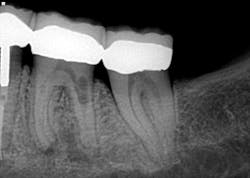

I almost missed this lesion on the radiograph

This actually has a huge bearing on dealing with resorption. External resorption versus internal resorption—when diagnosing, it makes all the difference. In my hands (and heart), I believe the only type that stands any chance whatsoever of treatment success is internal resorption. And even then, it depends on the extent of the damage.

When evaluating and discussing external resorption, I commonly tell my patients, “I cannot make your bones and gingiva stop eating the tooth. I do not have that power.” As we have all seen, external resorption can occur in various places and teeth. However, it almost always seems to be around the area of the alveolar crest, which, in my opinion, makes restoring it almost impossible. At least with internal resorption, one has a chance. You must be aggressive in cleaning the canal way beyond the typical endo and particularly in the areas of the defect. That, my friends, is where the microscope comes in very handy.

Unless it is caught on the early end, it does not matter. Once the resorptive damage has extended beyond a certain point, the prognosis drops precipitously, regardless of whether it started internally or externally. If communication of the defect occurs from internal to external or vice versa, I find that the prognosis goes from questionable to hopeless.